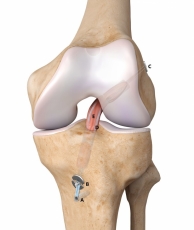

• Χειρουργικής Γόνατος, με έμφαση στην αρθροσκόπηση και ολική αρθροπλαστική